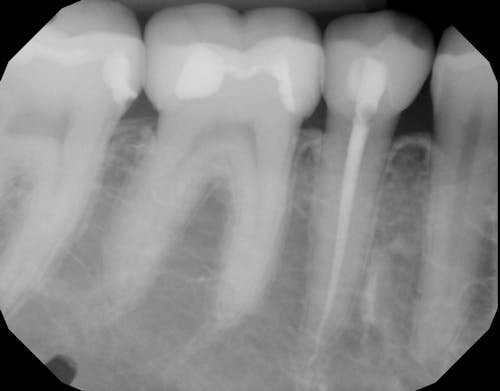

So, what is a root canal? When a damaged, chipped or diseased tooth—or teeth—causes pain, discomfort, or sensitivity, which cannot be reversed by other means, a root canal is often the best treatment. Essentially, a root canal removes and deactivates the nerve endings—or pain receptors—reversing your ability to feel pain in those teeth. This process saves your natural tooth while eradicating the pain.